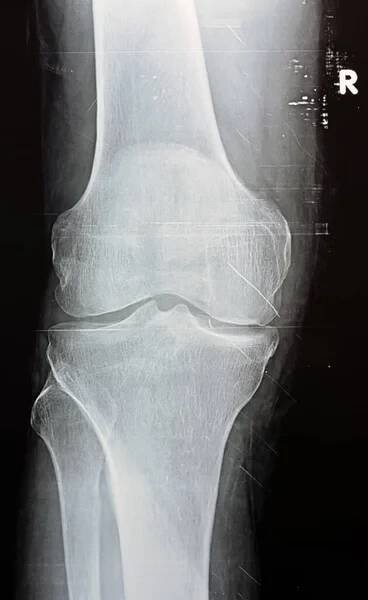

Prostý rentgen pravého kolena ukazuje zjevnou kloubní osteoartritidu dle Kellgrenova a Lawrencova systému pro klasifikaci osteoartritidy s definitivními osteofyty a zúžením prostoru — Stock obrázek